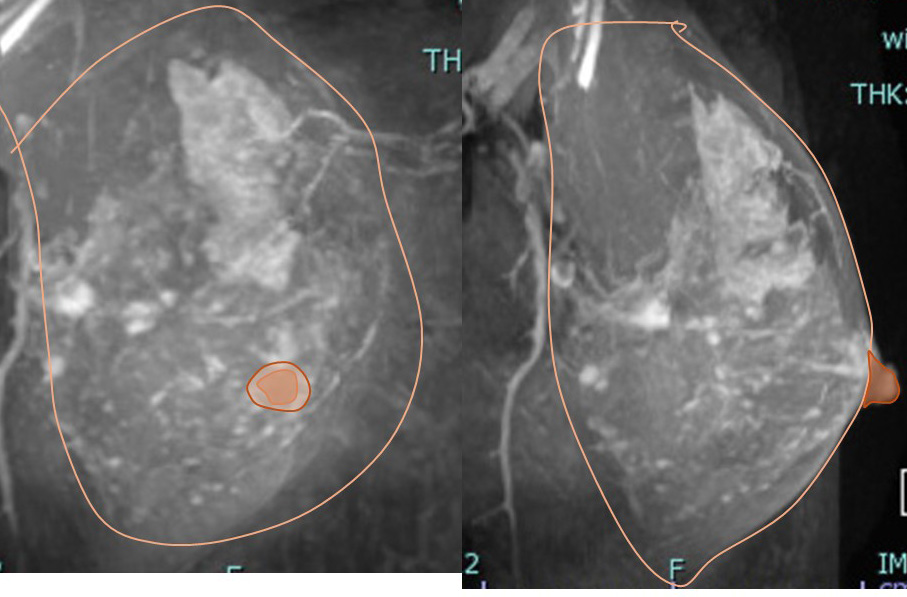

左 正面像(MRI) 右 側面像(MRI)

癌の拡がり(MRI)はこうなります。

拡がりに対してマージンをつけた切除範囲はこうなります。